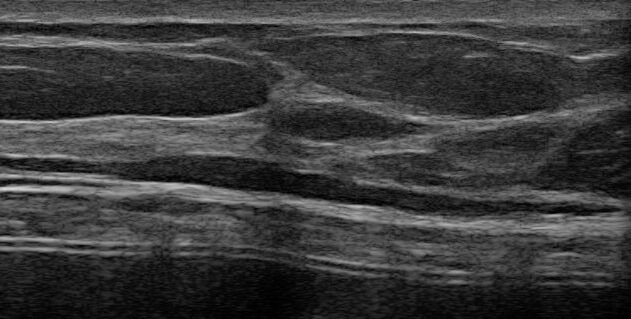

Using ultrasound to guide filler placement reduces the risk of complications and helps to monitor the filler over time, allowing you to decide when to dissolve or refresh the filler. Color and power Doppler are essential tools for managing vascular complications.